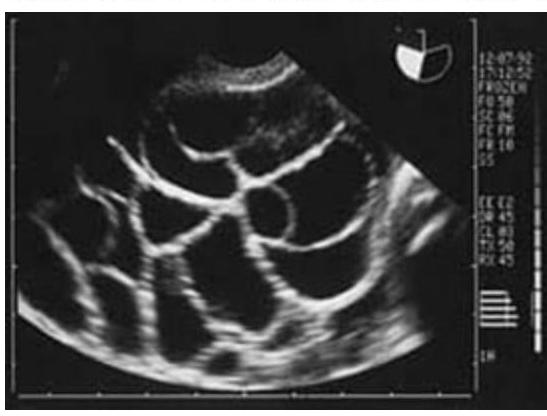

Question 4: A lady on treatment for infertility developed ascites, abdominal pain, and dyspnea. The ultrasound image is shown below. What is the most likely diagnosis?

Explanation: ***OHSS*** - The clinical presentation of a woman undergoing infertility treatment who develops **ascites**, **abdominal pain**, and **dyspnea** is classic for **Ovarian Hyperstimulation Syndrome (OHSS)**. The ultrasound image showing massively enlarged, multicystic ovaries with numerous follicles further confirms this diagnosis. - OHSS is an iatrogenic complication of **ovarian stimulation**, where ovaries become hyperstimulated, leading to **capillary permeability** and fluid shifts, resulting in ascites and potentially pleural effusions causing dyspnea. *PCOS* - While Polycystic Ovarian Syndrome (PCOS) involves multiple small follicles (usually 12 or more per ovary, each 2-9 mm in diameter), it typically does not present with acute symptoms like **ascites** and **dyspnea** unless severe OHSS occurs after ovulation induction in a woman with PCOS. - The ovaries in PCOS are generally smaller or normal size compared to the massively enlarged ovaries seen in the image, and the presence of significant ascites and dyspnea is not a direct feature of PCOS itself. *Theca lutein cyst* - **Theca lutein cysts** are usually **bilateral**, **multiloculated ovarian cysts** that result from exaggerated stimulation by **human chorionic gonadotropin (hCG)**, often seen in conditions like **gestational trophoblastic disease** or **multiple gestations**. - While they can be large and multicystic, the presentation with acute ascites and dyspnea in the context of infertility treatment points more specifically to OHSS. *Mucinous cystadenomas* - **Mucinous cystadenomas** are benign **epithelial ovarian tumors** that can grow very large and be multiloculated, but they are not typically associated with infertility treatment or the acute systemic symptoms of **ascites** and **dyspnea** via capillary leak syndrome. - Their presence would be coincidental rather than a direct complication of infertility therapy, and their fluid is usually thick and mucinous, enclosed within the cyst wall rather than causing diffuse fluid extravasation.